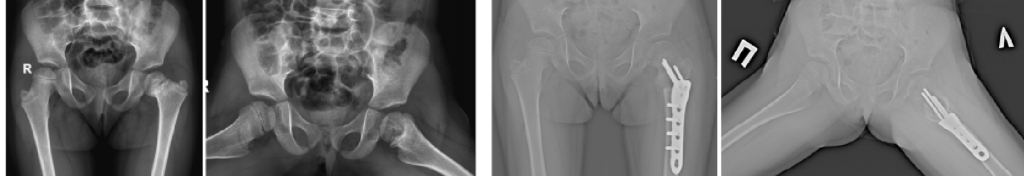

Main areas of surgical work: